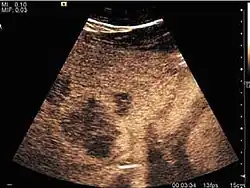

US examination is required to detect liver metastases in patients with oncologic history. In addition, the method can incidentally detect metastases in asymptomatic patients. Early identification (small sizes, small number) is important to establish an optimal course of treatment which can be complex (chemotherapy, radiofrequency ablation, surgical resection) but welcomed. In addition, discrimination of synchronous lesions that have a different nature is also important knowing that up to 25–50% of liver lesions less than 2 cm detected in cancer patients may be benign . US sensitivity for metastases detection varies depending on the examiner's experience and the equipment used and ranges between 40 and 80% . Sensitivity is conditioned by the size and acoustic impedance of the nodules. For a lesion diameter below 10 mm US accuracy is greatly reduced, reaching approx. 20%. Other elements contributing to lower US performance are: excessive obesity, fatty liver disease, hypomobility of the diaphragm, and certain patterns of hyperechoic or isoechoic metastases that can be overlooked or can mimic benign conditions. Conventional US appearance of metastases is uncharacteristic, consisting of circumscribed lesions, with clear, imprecise or "halo" delineation, with homogeneous or heterogeneous echo pattern. They can be single (often liver metastases from colonic neoplasm) or multiple. Echogenity is variable. When increased, they can compress the bile ducts (which may be dilated) and the liver vessels. Liver involvement can be segmental, lobar or generalized. In this situation a pronounced hepatomegaly occurs. Generally, metastases have non-characteristic Doppler vascular pattern, with few exceptions (carcinoid metastases). Cyst-adenocarcinoma metastases due to semifluid content may have a transonic appearance. When increasing, they can result in central necrosis. CEUS examination is a real breakthrough for detection and characterization of liver metastases.

Increased performance is based on identifying specific vascular patterns during the arterial phase and seeing metastases in contrast to normal liver parenchyma during the sinusoidal phase. CEUS increased accuracy is due to the different behavior of normal liver parenchyma (captures CA in Kuppfer cells) against tumor parenchyma (does not contain Kuppfer cells, therefore CEUS appearance is hypoechoic). To this adds the particularities of intratumoral circulation represented by a reduced arterial bed compared to that of the surrounding normal liver and the absence of the portal vessels . In terms of vascularity, metastases can be hypovascular (in gastric, colonic, pancreatic or ovarian adenocarcinomas) with hypoechoic pattern during arterial phase, and similar during portal venous and late phases, respectively hypervascular (neuroendocrine tumors, malignant melanoma, sarcomas, renal, breast or thyroid tumors) with hyperechoic appearance during arterial phase, with washout during the portal venous phase and hypoechoic pattern 30 seconds after injection.